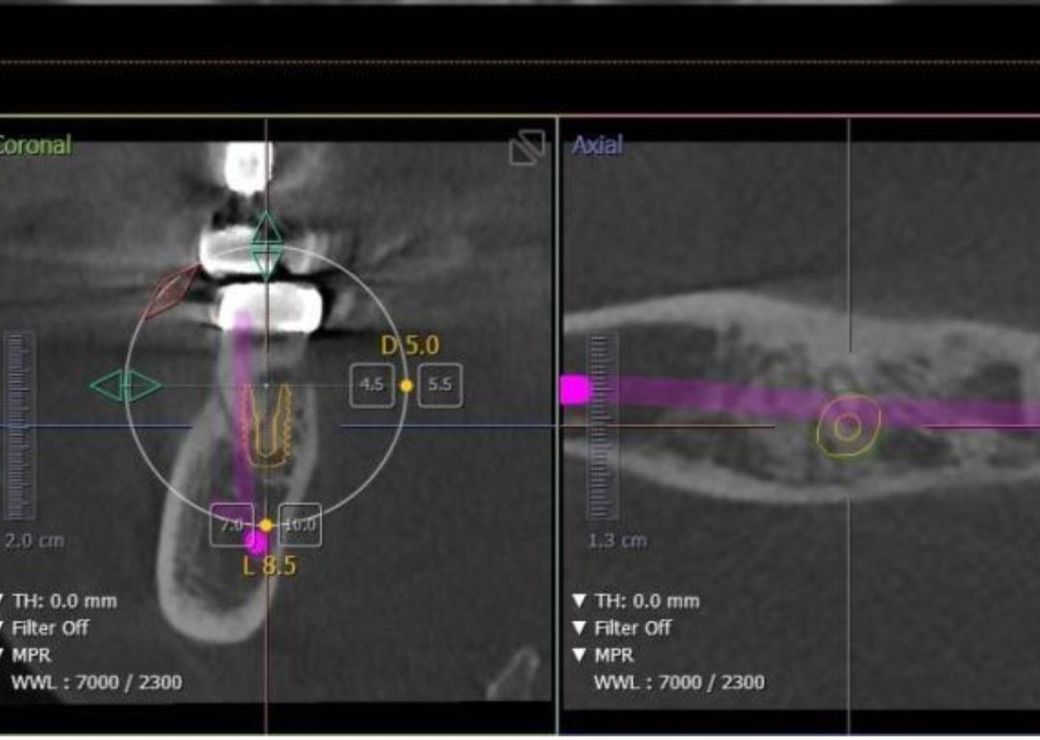

• 2번 째 사진

이미 거기 치과는 ct도 찍고, 임플란트로 계획을 잡은것 같네요 치료계획에 공감대 형성되지 않으신다면 다른 치과, 대학치과병원 가보세요 여기서 과잉진료다 라고 판단해줘도 그 치과에 가서 따지거나 할 순 없답니다

뼈는 녹아 있는 것이 확인됩니다. 치아를 살리시고 싶으시면 잇몸치료 선행해보셔도 괜찮습니다.